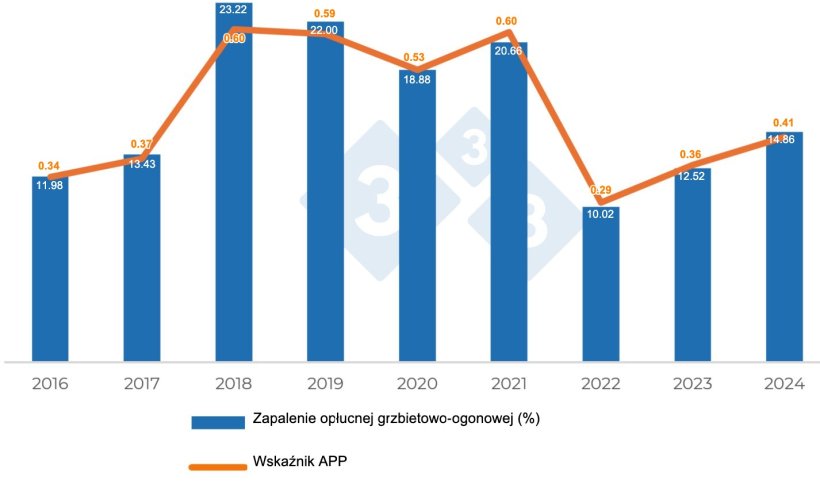

A co z zapaleniem opłucnej? Jak się rozwinęło?

W odniesieniu do zapalenia opłucnej dogrzbietowo-doogonowej związanego z APP nie ma wyraźnego wzorca ewolucji, a raczej występują wahania w częstości występowania zmian chorobowych. Wskaźnik ten wzrósł z 11,98% w 2016 r. do 23,22% w 2018 r., a następnie spadł do poprzedniego poziomu w 2022 r., chociaż wydaje się, że w ostatnich dwóch latach objętych oceną ponownie nastąpił wzrost częstości występowania zmian chorobowych (Tabela 1 i Wykres 2).

Wykres 2. Ewolucja zmian chorobowych zgodnych z Actinobacillus pleuropneumoniae.

W przypadku zmian związanych z APP wzrost częstości występowania zmian obserwowany od 2018 r. może być związany zarówno ze zmniejszeniem powszechnego stosowania antybiotyków w fazie odchowu, jak i przejściem do fazy tuczu, a także ze wzrostem średniej długości laktacji, który miał miejsce w tych latach. Jednakże ta zmienność częstości występowania i nasilenia zmian chorobowych raczej nie ma wyraźnego wzorca, biorąc pod uwagę istnienie różnych serotypów o różnym stopniu zjadliwości, których częstość występowania również zmienia się w czasie. Niemniej jednak oba te fakty mogą być ze sobą powiązane, co wymagałoby przeprowadzenia badań łączących poziom nasilenia zmian chorobowych z częstością występowania różnych serotypów APP.